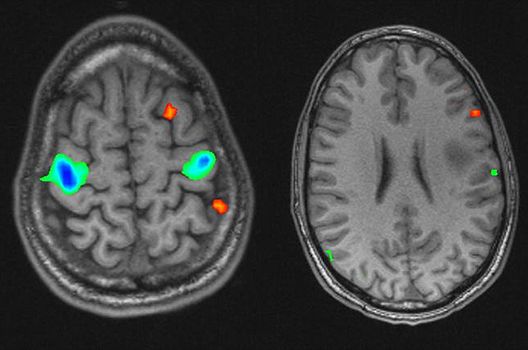

- Funktionelle Bildgebung des Gehirns (fMRT)

Die Schwerpunkte in der MR-Forschung liegen in der multiparametrischen und funktionellen Bildgebung bei onkologischen und anderen, neuroradiologischen Fragestellungen und umfassen die Anwendung modernster MR-Verfahren sowie die Untersuchung an Hochfeld-Geräten.

Die Magnetresonanztomographie (MRT) ist ein Verfahren, bei dem durch magnetische Kräfte Bilder des Körperinneren angefertigt werden. In der Neuroradiologie können manchmal kleinste Veränderungen schwere Folgen haben; daher forschen wir an der Entwicklung hochauflösender MRT-Sequenzen, mit denen diese Prozesse und auch einzelne Nervenfaserbahnen sichtbar gemacht werden können. Darüber hinaus sind bei vielen Erkrankungen des Gehirns die Blutgefäße betroffen. Daher arbeiten wir an der Neu- und Weiterentwicklung von MRT-Sequenzen zur Darstellung der Blutgefäße und zur Blutflussanalyse (sog. „Angio-MRT“). Einen besonderen Forschungsschwerpunkt unserer Klinik stellen die MR-Protonenspektroskopie und die funktionelle MRT dar, mit denen die Analyse einzelner chemischer Substanzen im Hirngewebe oder die Darstellung ausgewählter Hirnfunktionen möglich ist.